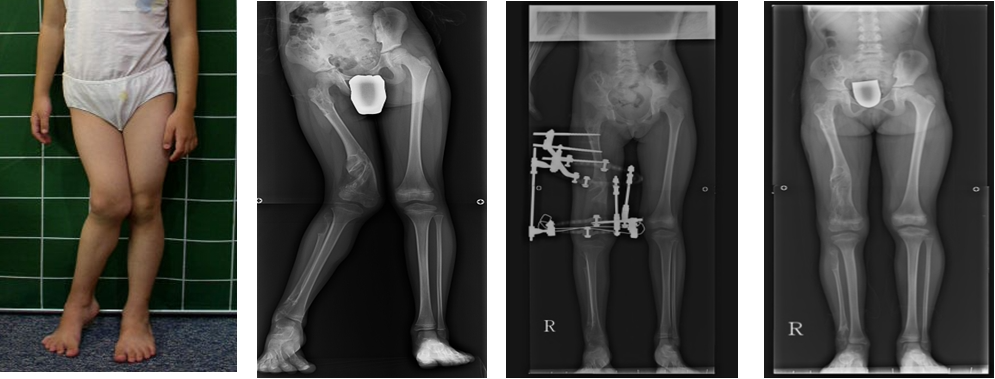

공지 하지변형에 대한 대퇴골교정관리자-안쪽으로 휜 오른쪽다리를 허벅지뼈에서 교정하였습니다. Perform correction surgery on the right leg that has varus deformity at femur.다음글공지 발의 변형에 대한 교정 1이전글공지 하지변형에 대한교정목록